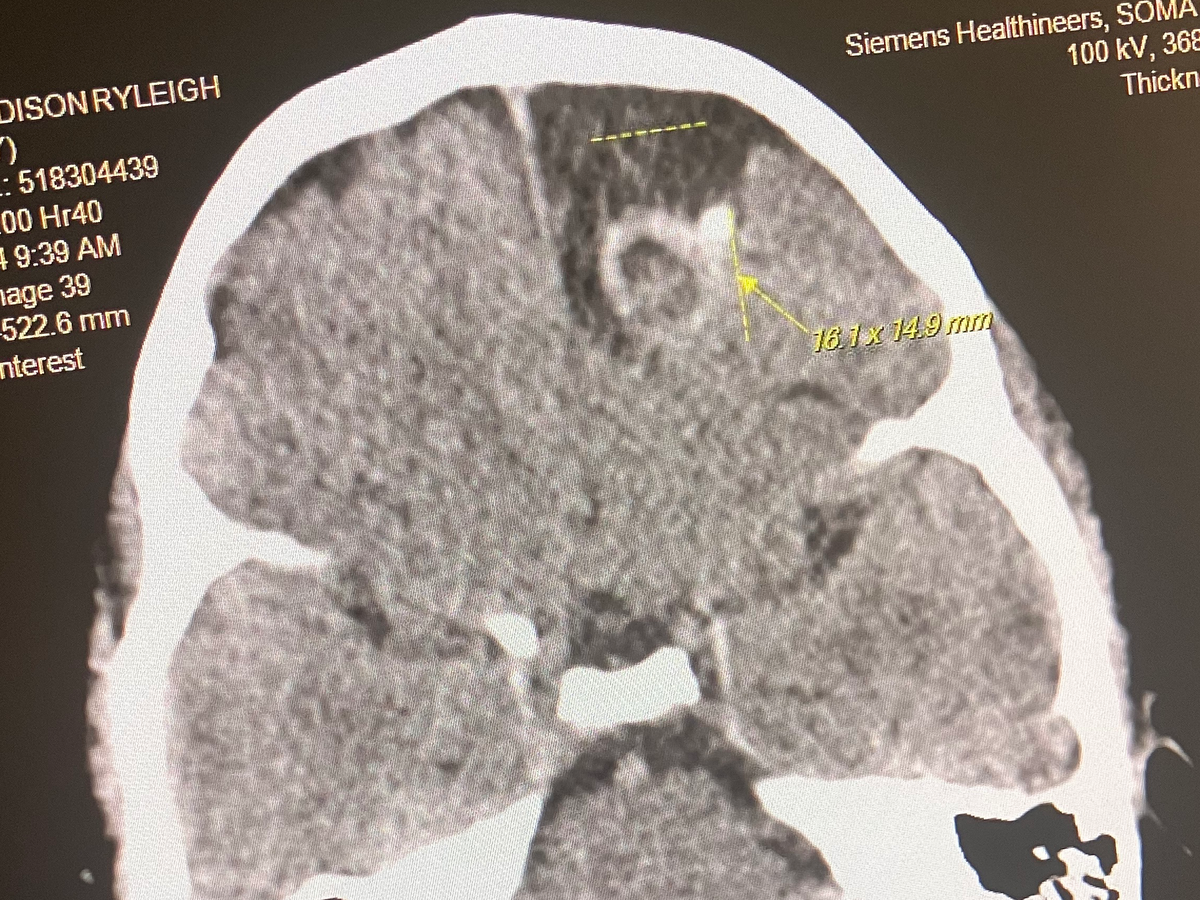

The next morning, Addison woke up saying that her head was hurting only on the left side. I immediately took her to Franklin Memorial Hospital, where they performed a CT scan. The CT scan came back showing that Addison had no brain matter in the left frontal lobe of her brain. FMH sent us directly back to RMH, where they performed an MRI that confirmed what the CT scan had shown earlier that same day. They also performed an EEG, which showed that she was not only having seizures while asleep but her brain was trying to go into seizures while awake as well. We went to Carilion Neurology, where they performed yet another EEG and stated they were seeing the same things that they had confirmed on the EEG performed in the ED.

Since then, we have been to UVA, where Dr. Grabb told us that Addison would have to have surgery to take out a “Carnivorous Malformation” in her brain. He stated that this “CM” is very much like a tumor, only it does not grow. I am starting this GoFundMe to get help with Addison as well as bills while I am going to be out of work to care for her. Any little bit will help in any way you can. Whether that be donating or simply praying!! We could definitely use all the prayers we can get at this time!!❤️